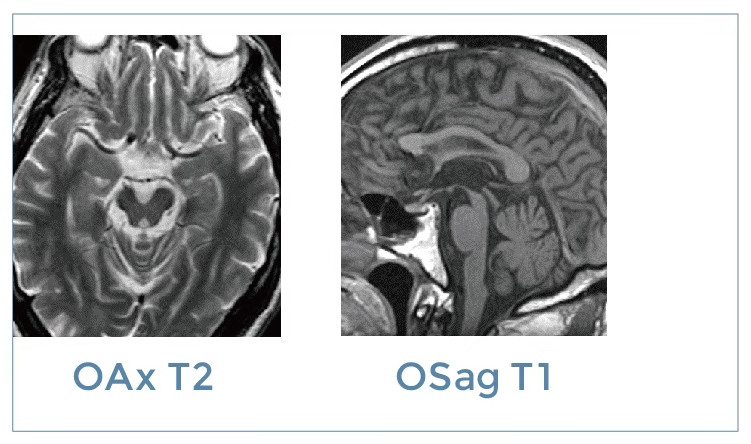

【朗润影像档案】20191108磁共振影像病例结果讨论

【朗润影像档案】磁共振影像病例分享(编号20191108)